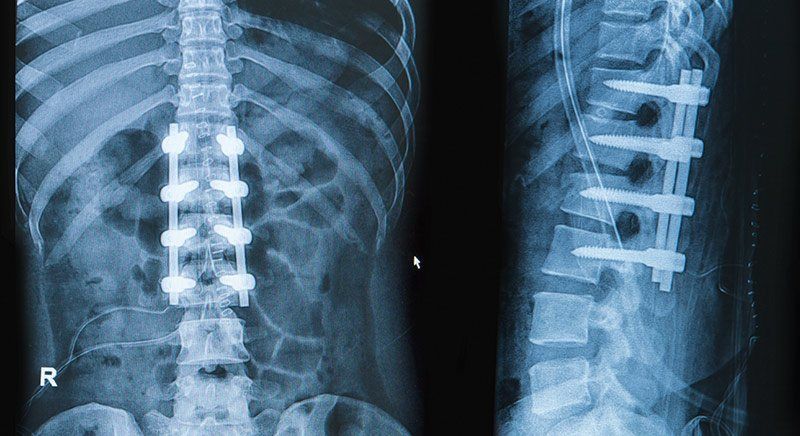

Patología y cirugía de la columna vertebral

En nuestra clínica de traumatología le ofrecemos una serie de tratamientos médicos y quirúrgicos con los que nos ocupamos de su raquis cervical y lumbar, la cual afecta a la artrosis, a la hernia discal, a la estenosis de canal, espondilolistesis, escoliosis y puede causar fracturas.

Por eso, las técnicas que aplicamos para los pacientes son de invasión mínima y están muy avanzadas tecnológicamente, como las infiltraciones facetarias, rizólisis, bloqueos nerviosos y transforaminales, pregúntenos.